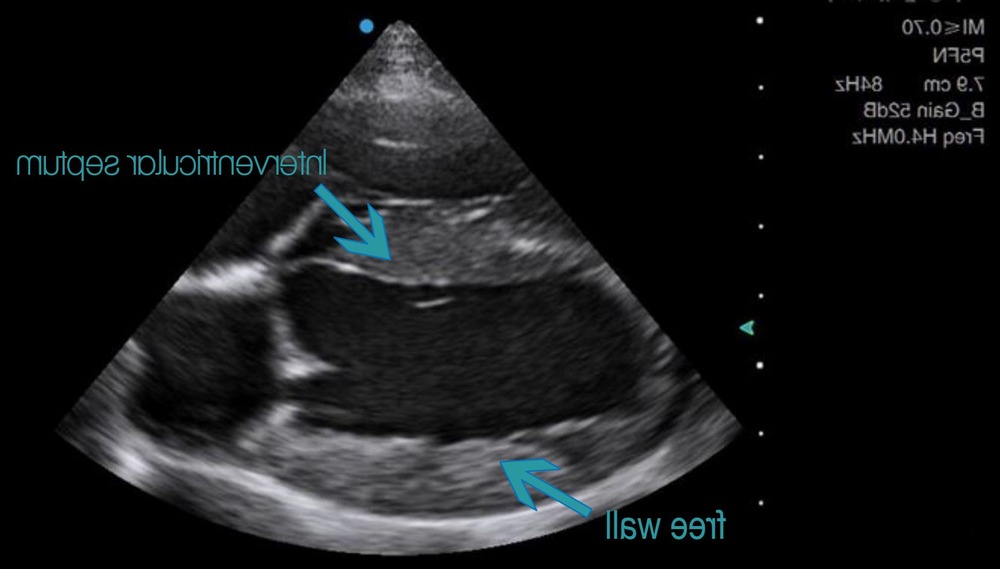

The test that matters most for HCM is an echocardiogram (ultrasound of the heart). It allows measurement of wall thickness, chamber sizes, filling patterns, and assessment for dynamic outflow obstruction or valve leakage. In many cases, your vet may recommend referral to a veterinary cardiologist, because subtle distinctions in cardiac ultrasound interpretation can change what “thickening” means clinically.1, 8

These are not “extra for the sake of it”. They help separate primary cardiomyopathy from other causes of thickened walls, and they help stage risk, which is what guides treatment decisions.1, 8